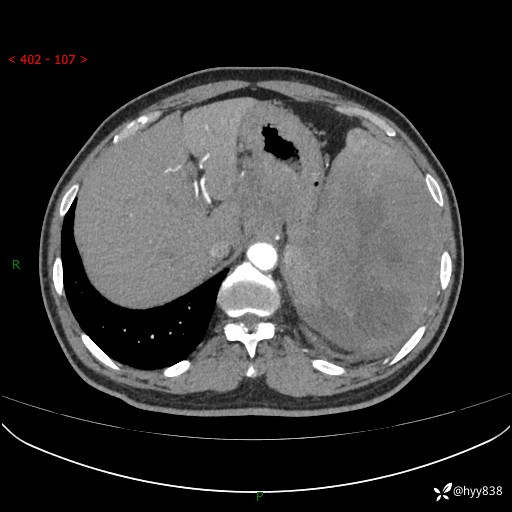

上腹部CT平扫

增强(动脉期+静脉期)